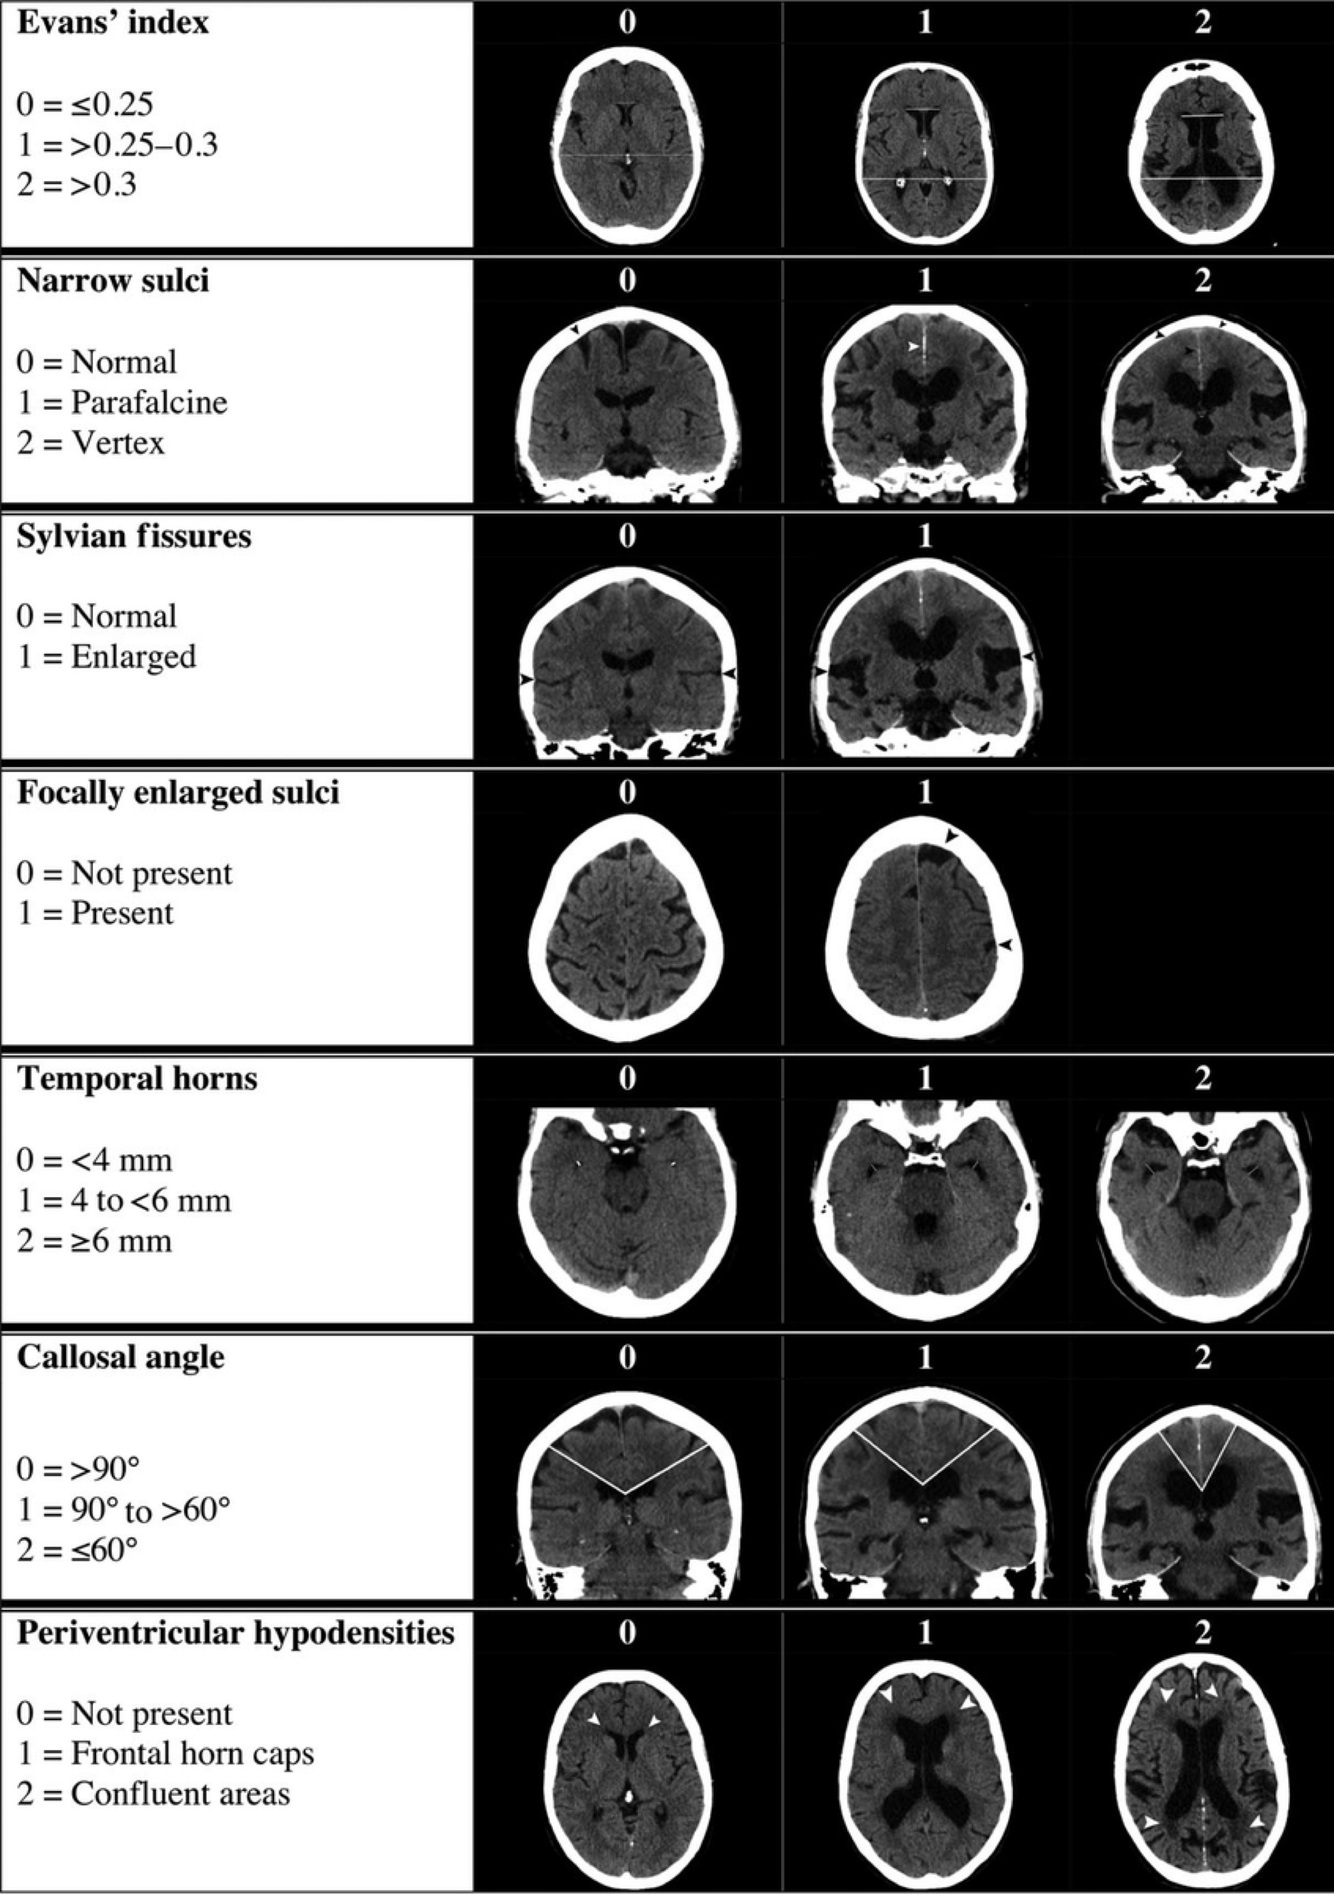

What is the Evans Index ?

The ratio of maximum width of a frontal herns to maximum inner skull diameter

• 0.20-0.25»_space; normal

• 0.25-0.30»_space; possible/early ventriculomegaly

• > 0.30»_space; ventriculomegaly

In iNPH what you gonna see in sagital view ct ?

A

corpus callosum angle

The callosal angle has been proposed as a useful marker of patients with idiopathic normal pressure hydrocephalus (iNPH), helpful in distinguishing these patients from those with ex-vacuo ventriculomegaly (see hydrocephalus versus atrophy).

It should be noted that there is nothing magical about this measurement, but rather it is merely a quantifiable measurement of the morphology of iNPH characterized by enlarged widening of the Sylvian fissures and cisterns with crowding of the gyri at the vertex.

Measurement

Ideally, the angle should be measured on a coronal image perpendicular to the anterior commissure - posterior commissure (AC-PC) plane at the level of the posterior commissure 1,2.

Interpretation

In general patients with iNPH have smaller angles than those with ventriculomegaly from atrophy or normal controls.

A normal value is typically between 100-120°. In patients with iNPH that value is lower, between 50-80° 2.